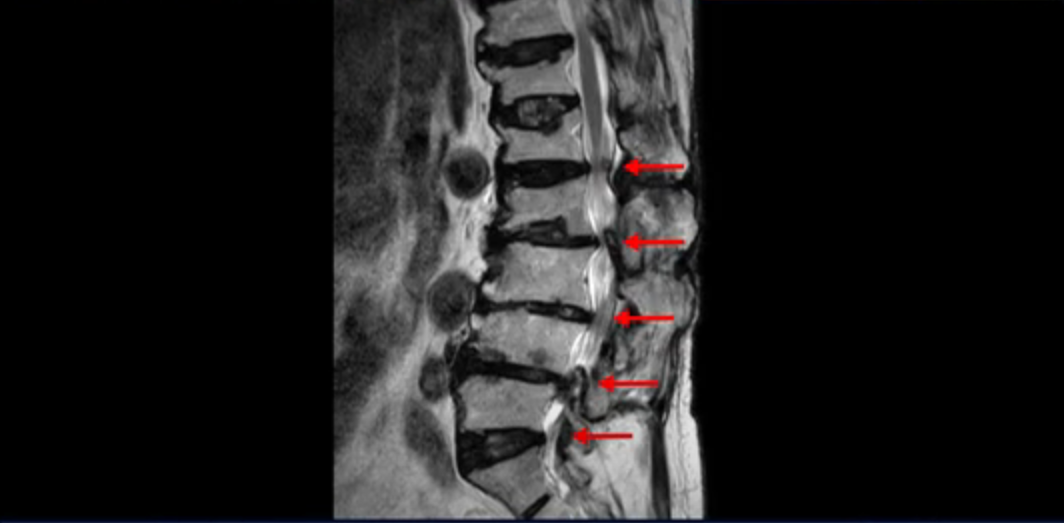

이 환자분은 허리 여러 마디가 다 안 좋아서 오랫동안 허리가 아프셨고 허리도 일찌감치 굽으셨습니다. MRI를 보시면 허리 여러 마디가 심하게 안 좋습니다.

보시다시피 4번 5번 마디에는 심한 중심성 협착이 있고

1번 2번,

2번 3번,

3번 4번에도 중심성 협착이 있습니다.

또 신경 가지가 빠져나가는 추간공도 좁아져 있습니다. 이런 이유로 환자분의 다리가 저리고 아픈 겁니다.

또한 척추뼈 여러 개가 압박 골절과 변형으로 찌그러져 있고

골다공증도 심하시고 보시다시피 근육량이 너무 적습니다. 근육이 정상적인 분들과 비교해보면 근육이 얼마나 적은지 알 수 있습니다.